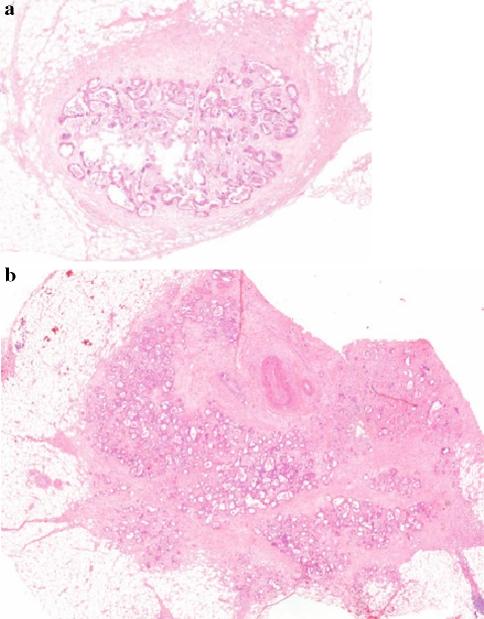

The medical files of 870 CRC patients were reviewed. Number, size, shape, and location pattern of all ITDs in node-negative patients were examined in relation to involvement of vascular structures and nerves. The correlation between ITDs and the development of recurrent disease was investigated.

Disease recurrence was observed in 50.0% of stage II patients with ITDs (13 of 26), compared with 24.4% of stage II patients without ITDs (66 of 270) (P < .01). Disease-free survival of ITD-positive stage II patients was comparable with that of stage III patients. Also within stage III, more recurrences were observed in ITD-positive patients compared with ITD-negative patients (65.1 vs. 39.1%, respectively). No correlation was found between size of ITDs and disease recurrence. More recurrences were seen in patients with irregularly shaped ITDs compared with patients with 1 or more smooth ITDs present.